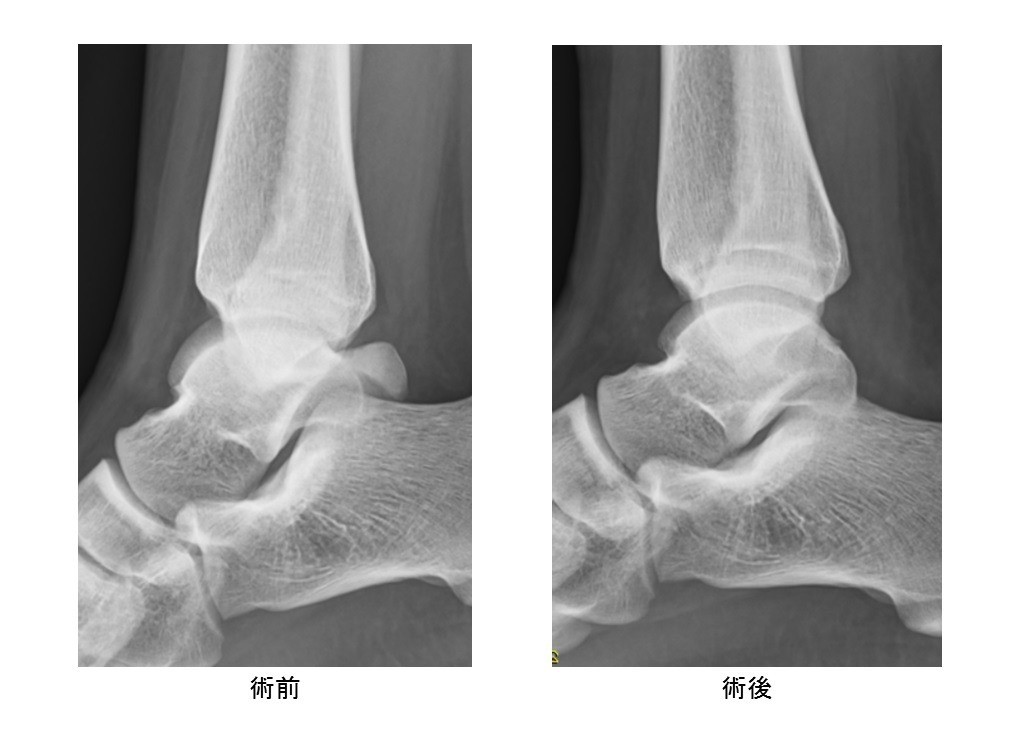

• 距骨骨軟骨損傷(離断性骨軟骨炎)

スポーツ整形

距骨骨軟骨損傷(離断性骨軟骨炎)